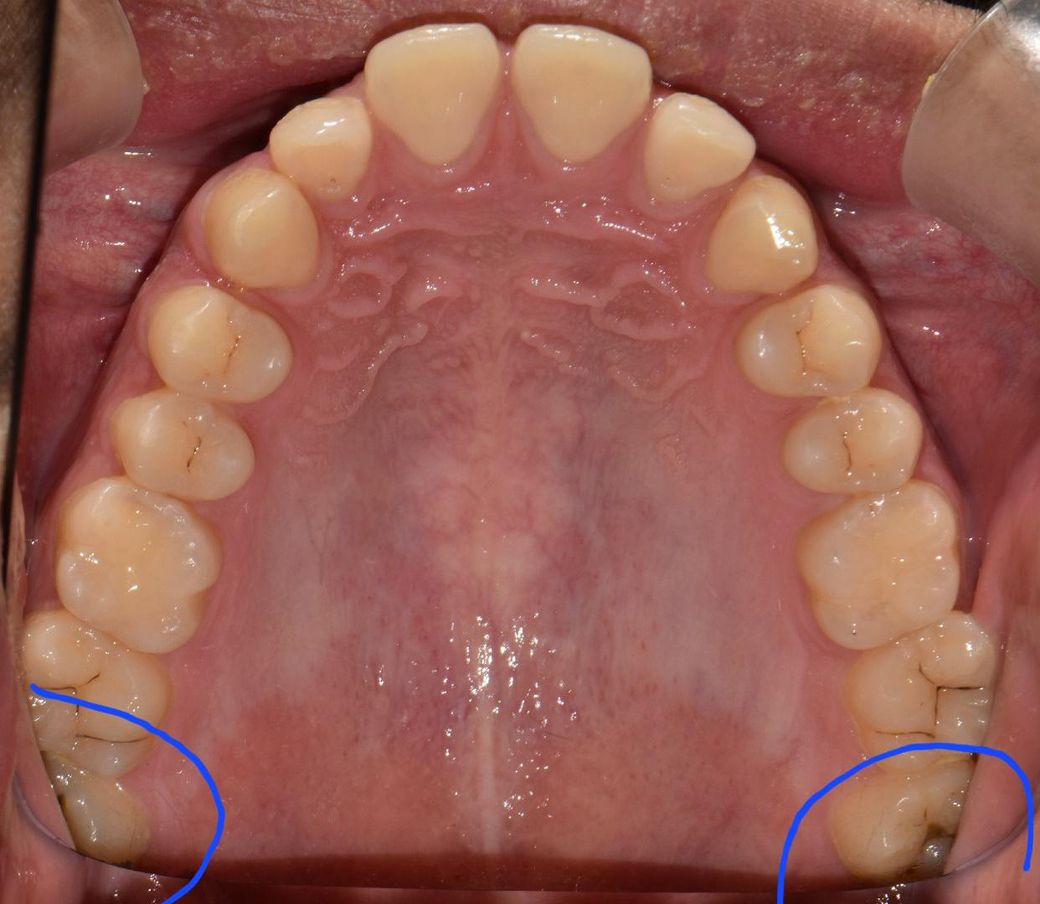

사진속 구강상태에서 초기 정지우식이라고합니다. 근데 재광화가풀려 며칠동안 조금이라도 정지우식이 다시 진행되었다면, 진행된지 고작 2주정도 지났다고 쳐도 인레이가 필요한치아가 있나요? 많이 진행되지않고 2주동안 이제막 충치가번지기 시작하는경우, 레진인지 인레이인지 궁금합니다

• 2번 째 사진